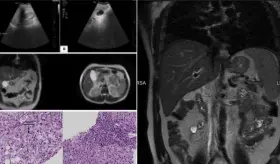

Las imágenes sugerían infiltración linfomatosa, pero la esplenectomía ...